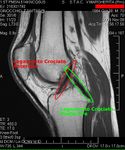

MRI

Both anterior cruciate ligament (ACL) and posterior cruciate ligaments (PCL) are hypointense on both T1 and T2 weighted images of MRI. However, some high signal striations are often seen at the distal part of the ACL, making ACL higher intensity than PCL on MRI scans.[22]

Both anterior cruciate ligament (ACL) and posterior cruciate ligaments (PCL) are hypointense on both T1 and T2 weighted images of MRI. However, some high signal striations are often seen at the distal part of the ACL, making ACL higher intensity than PCL on MRI scans.[20]

Cruciate ligaments